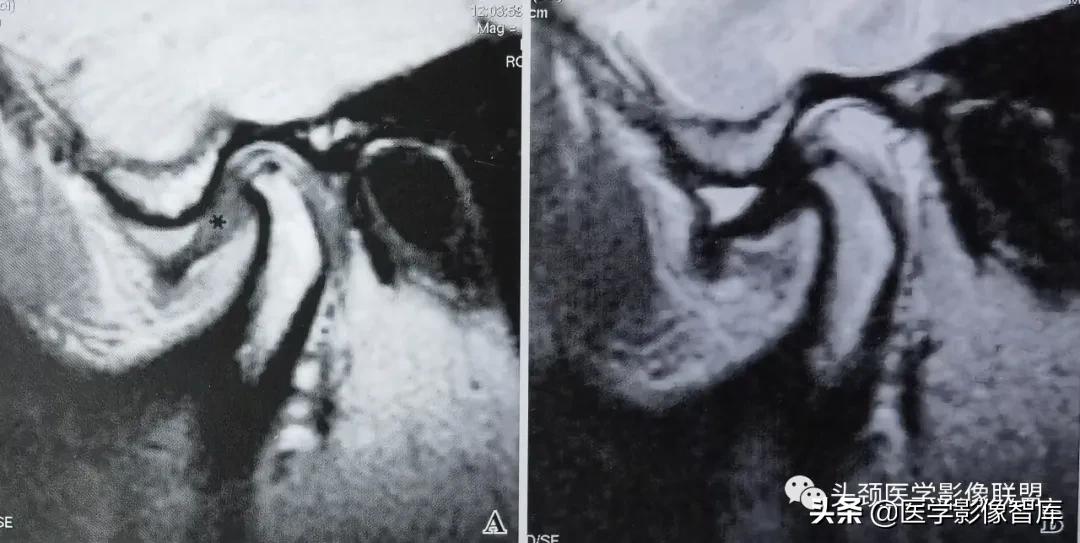

图2 不可复性关节盘前移

A. 矢状面闭口PDWI示关节盘后带(黑星)位于髁突前方;B.矢状面开口T2WI示:关节盘随下颌髁突前移,仍位于其前方。关节盘无变形,盘后附着相对拉长。关节上腔内有中量积液。下颌髁突活动度小。

不可复性盘前移位的主要临床表现为髁突活动受限。它是指闭口位时,关节盘位于下颌髁突横嵴顶的前方;张口时,随着下颌髁突向前移动,撞击关节盘后带,迫使其进一步向前移动。关节盘不能向后反跳越过髁突,因此也就不能恢复正常的盘一髁关系。不可复性盘前移位的MRI表现特点为:矢状面闭口位上 (图2A) ,低信号的关节盘明显位于髁突横嵴顶12点位的前方,关节盘后双板区被明显牵拉变长,并移位于髁突横嵴顶12点位的前方;矢状面张口位上 (图2B) ,关节盘双板区因拉伸而变直,关节盘仍位于下颌髁突的前方,不能恢复正常的盘一髁关系。